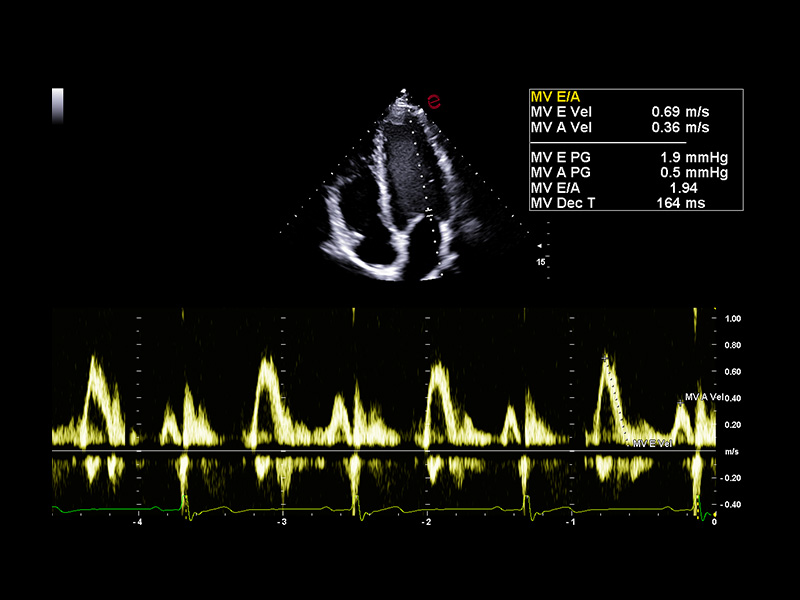

AI-based cardiac measurements for speed and consistency

Esaote’s AutoEF and AutoCM tools are designed to bring a step ahead in the device use experience. With advanced AI algorithms, AutoEF automatically recognizes apical views and traces endocardial borders offering a proposal of left ventricular volumes and ejection fraction in just seconds. AutoCM complements this by automatically suggesting ventricular wall thickness, internal diameters, and derived values such as LV mass and fractional shortening directly from parasternal views. Moreover, AutoCM assists cardiologists by automatically recommending a calculation of the E/A wave ratio of the mitral valve, providing crucial information on diastolic function.

Together, these tools help clinicians to obtain accurate, guideline-aligned measurements in a fast way, maintaining diagnostic evidence at the top. AutoEF and AutoCM automate key functional and structural measurements—such as ejection fraction, LV volumes, wall thickness, and LV mass— making a smooth workflow, especially in high-throughput clinics.